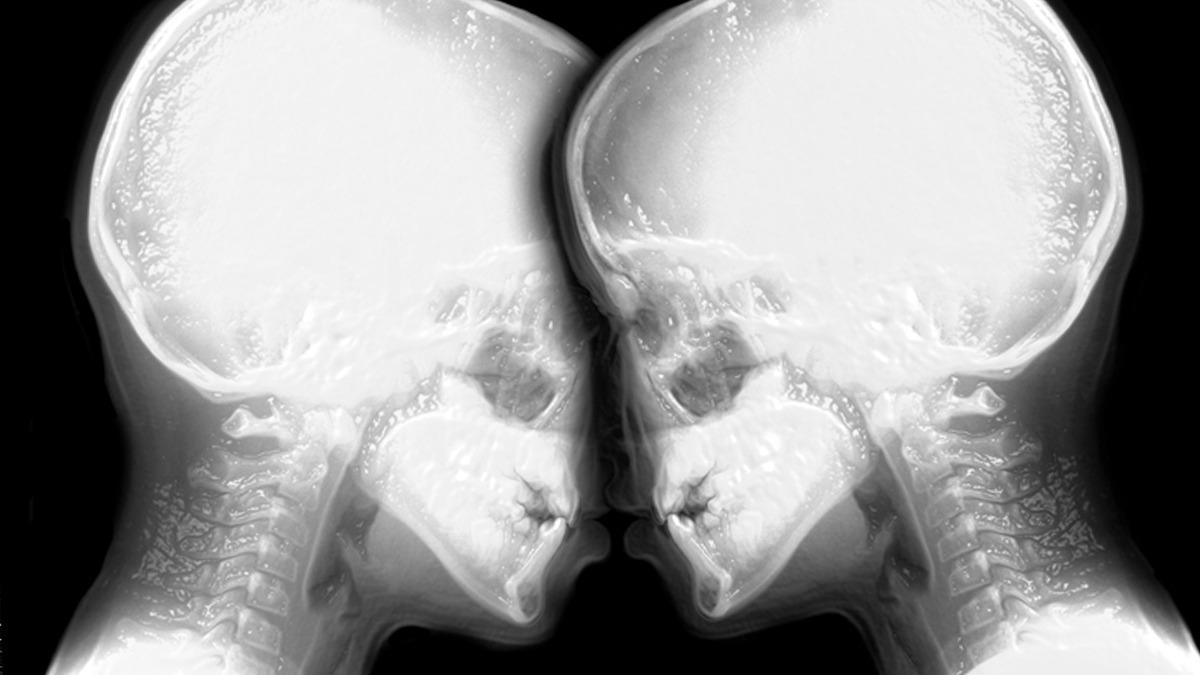

1991 yılında Hollanda’da yapılan sıra dışı bir bilimsel deney, insan vücuduna dair bilinenleri değiştirdi. Ida Sabelis ve partneri Jupp, bilimsel araştırma kapsamında dönemin ilk MR cihazlarından birinde görüntülenmeyi kabul etti. Amaç, cinsel birleşme sırasında vücutta neler olduğunu net biçimde gözlemlemekti.

Deney, Hollandalı bilim insanı Menko Victor van Andel tarafından yürütüldü. Elde edilen görüntüler, 1999 yılında British Medical Journal (BMJ) dergisinde yayımlandı ve tıp dünyasında büyük ses getirdi. Çalışma, aradan yıllar geçmesine rağmen hâlâ ilgiyle okunuyor.

Elde edilen görüntüler sayesinde ortaya çıkan bulgular, yüzyıllardır süregelen anatomik kabullerin sorgulanmasına neden oldu.